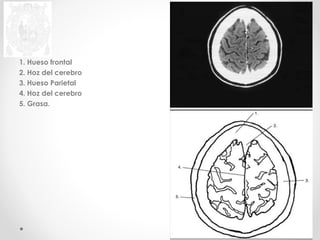

1. Hueso frontal

2. Grasa

3. Hoz del cerebro

4. LCR

5. Hueso Parietal

6. Lóbulo Parietal

7. Lóbulo Occipital

8. Lóbulo Frontal

2. Hoz del cerebro

3. Hueso Parietal

4. Hoz del cerebro

5. Grasa.